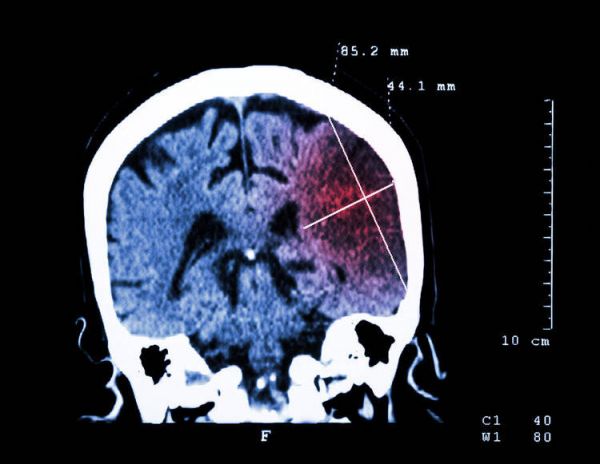

23岁的小林是互联网工作者,连续奋斗了好几个通宵后,总算有机会休息,可当晚在浴室洗澡时,小林却突然昏迷倒地,清醒发觉自己既不能说话,右侧身体也无法动弹,室友发现后赶紧将他送到了医院,并被确诊急性脑梗。

成人血液中HCY超过10μmol/L就能诊断为高同型半胱氨酸血症,而HCY升高会导致动脉粥样硬化的形成,斑块堵塞血管后就会导致心血管事件的发生,特别是高同型半胱氨酸血症合并高血压时,即可诊断为H型高血压,此时患者脑卒中的风险也会增高。